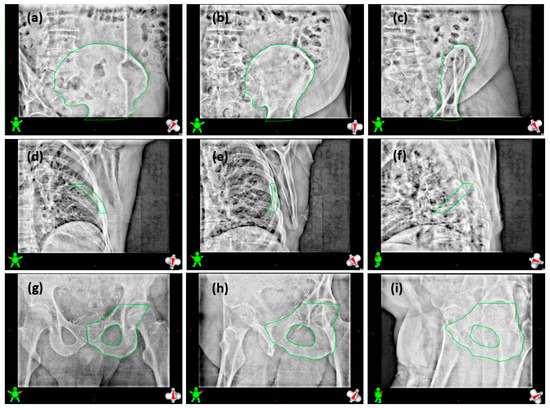

2.2. Patient Study

2.3. Analysis Method

3.2. Patient Study